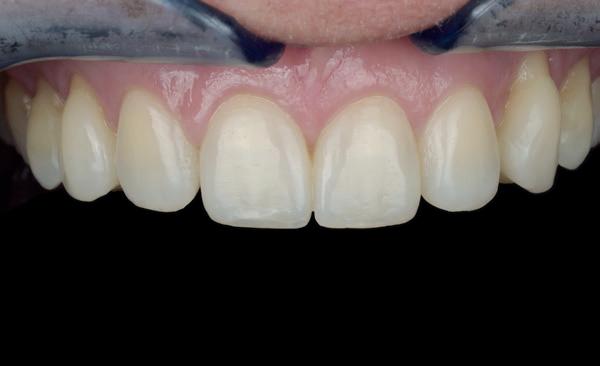

De pasvorm van de transparante mal wordt opnieuw gecontroleerd en vervolgens kunnen elementen 11 en 21 geïnjecteerd worden. Het is niet aan te raden om beide elementen tegelijk te injecteren, omdat ze dan volledig aan elkaar vast zullen zitten. Het is beter om ook hier om-en-om te werken. Eerst wordt element 21 geïnjecteerd en de buurelementen afgedekt met teflon (afbeelding 29). Dit element wordt geïnjecteerd met G’aenial Universal Injectable A2 (afbeelding 30). De overmaat wordt verwijderd en alle stappen worden herhaald bij element 11 (afbeelding 31). Nadat alle overmaat is verwijderd, de randaansluitingen zijn gecontroleerd met floss en de composiet op hoogglans is gepolijst, wordt de rubberdam verwijderd. Door het gebruik van rubberdam krijg je retractie van de gingiva, hierdoor zie je soms direct na behandeling nog steeds kleine black triangles. Daarnaast drogen de elementen uit, waardoor er sprake kan zijn van een kleurverschil tussen de elementen en de composiet. Waarschuw je patiënt hier altijd voor; binnen 24 - 48 uur kunnen ze het eindresultaat pas echt goed beoordelen.

In deze casus is een groot verschil zichtbaar in de incisale rand van de 11 (afbeelding 32). Bovenstaande wordt met de patiënt besproken en we spreken af om bij de evaluatie (twee weken later) de situatie te beoordelen. Als het nodig is, kunnen we dan element 11 nog iets aanpassen door gebruik te maken van een meer opaak composiet (G’aenial A’chord OA2, GC).

De patiënt wordt twee weken later gezien voor evaluatie. De gingiva ziet er weer keurig uit en de elementen hebben weer hun natuurlijke kleur gekregen.

32: Direct na het verwijderen van de rubberdam zien we retractie van de gingiva en uitdroging van de elementen.

33: Evaluatie na twee weken. We zien een mooie integratie van de composiet.

De overgang op element 11 valt nauwelijks nog op en we besluiten om dit zo te laten. De patiënt is in de tussentijd bij de orthodontist geweest, daar is een retentiedraad geplaatst.

De hybride injectietechniek is een ontzettend mooie techniek om te gebruiken wanneer je wel gebruik wilt maken van de voordelen van de injectietechniek, maar geen monochromatische restauratie wil krijgen. Het is echter, zeker in combinatie met diastemen, een zeer behandelaars gevoelige techniek. Het is daarom belangrijk om erg netjes en in kleine laagjes te werken en na elke stap opnieuw de pasvorm van de mallen te controleren.